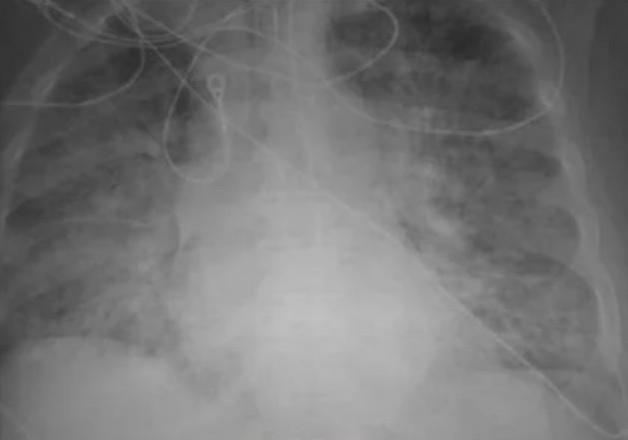

Dr Ghassan Kamel, director of the Medical ICU at SSM Health Saint Louis University Hospital in Missouri revealed that healthy lungs usually appear black in X-rays. According to Kamel, the dark contrast indicates that the lungs are full of oxygen and are performing well.

However, this was not the case for a person who contracted Covid infection before getting vaccinated. The lungs of the unvaccinated person appear milky-white on the X-rays, which indicates that the lungs have suffered extensive damage, build-up of mucus, and lack of sufficient oxygen. Covid patients who are unvaccinated may develop severe complications, and sometimes, they need to be put on life support as their lungs simply struggle to keep them alive.

"With the X-ray looking like that, they'd definitely at least require oxygen, and sometimes they would require more than just oxygen. They might require the ventilator or get intubated on mechanical ventilation, sedated, and basically on life support," Kamel told KSDK News.